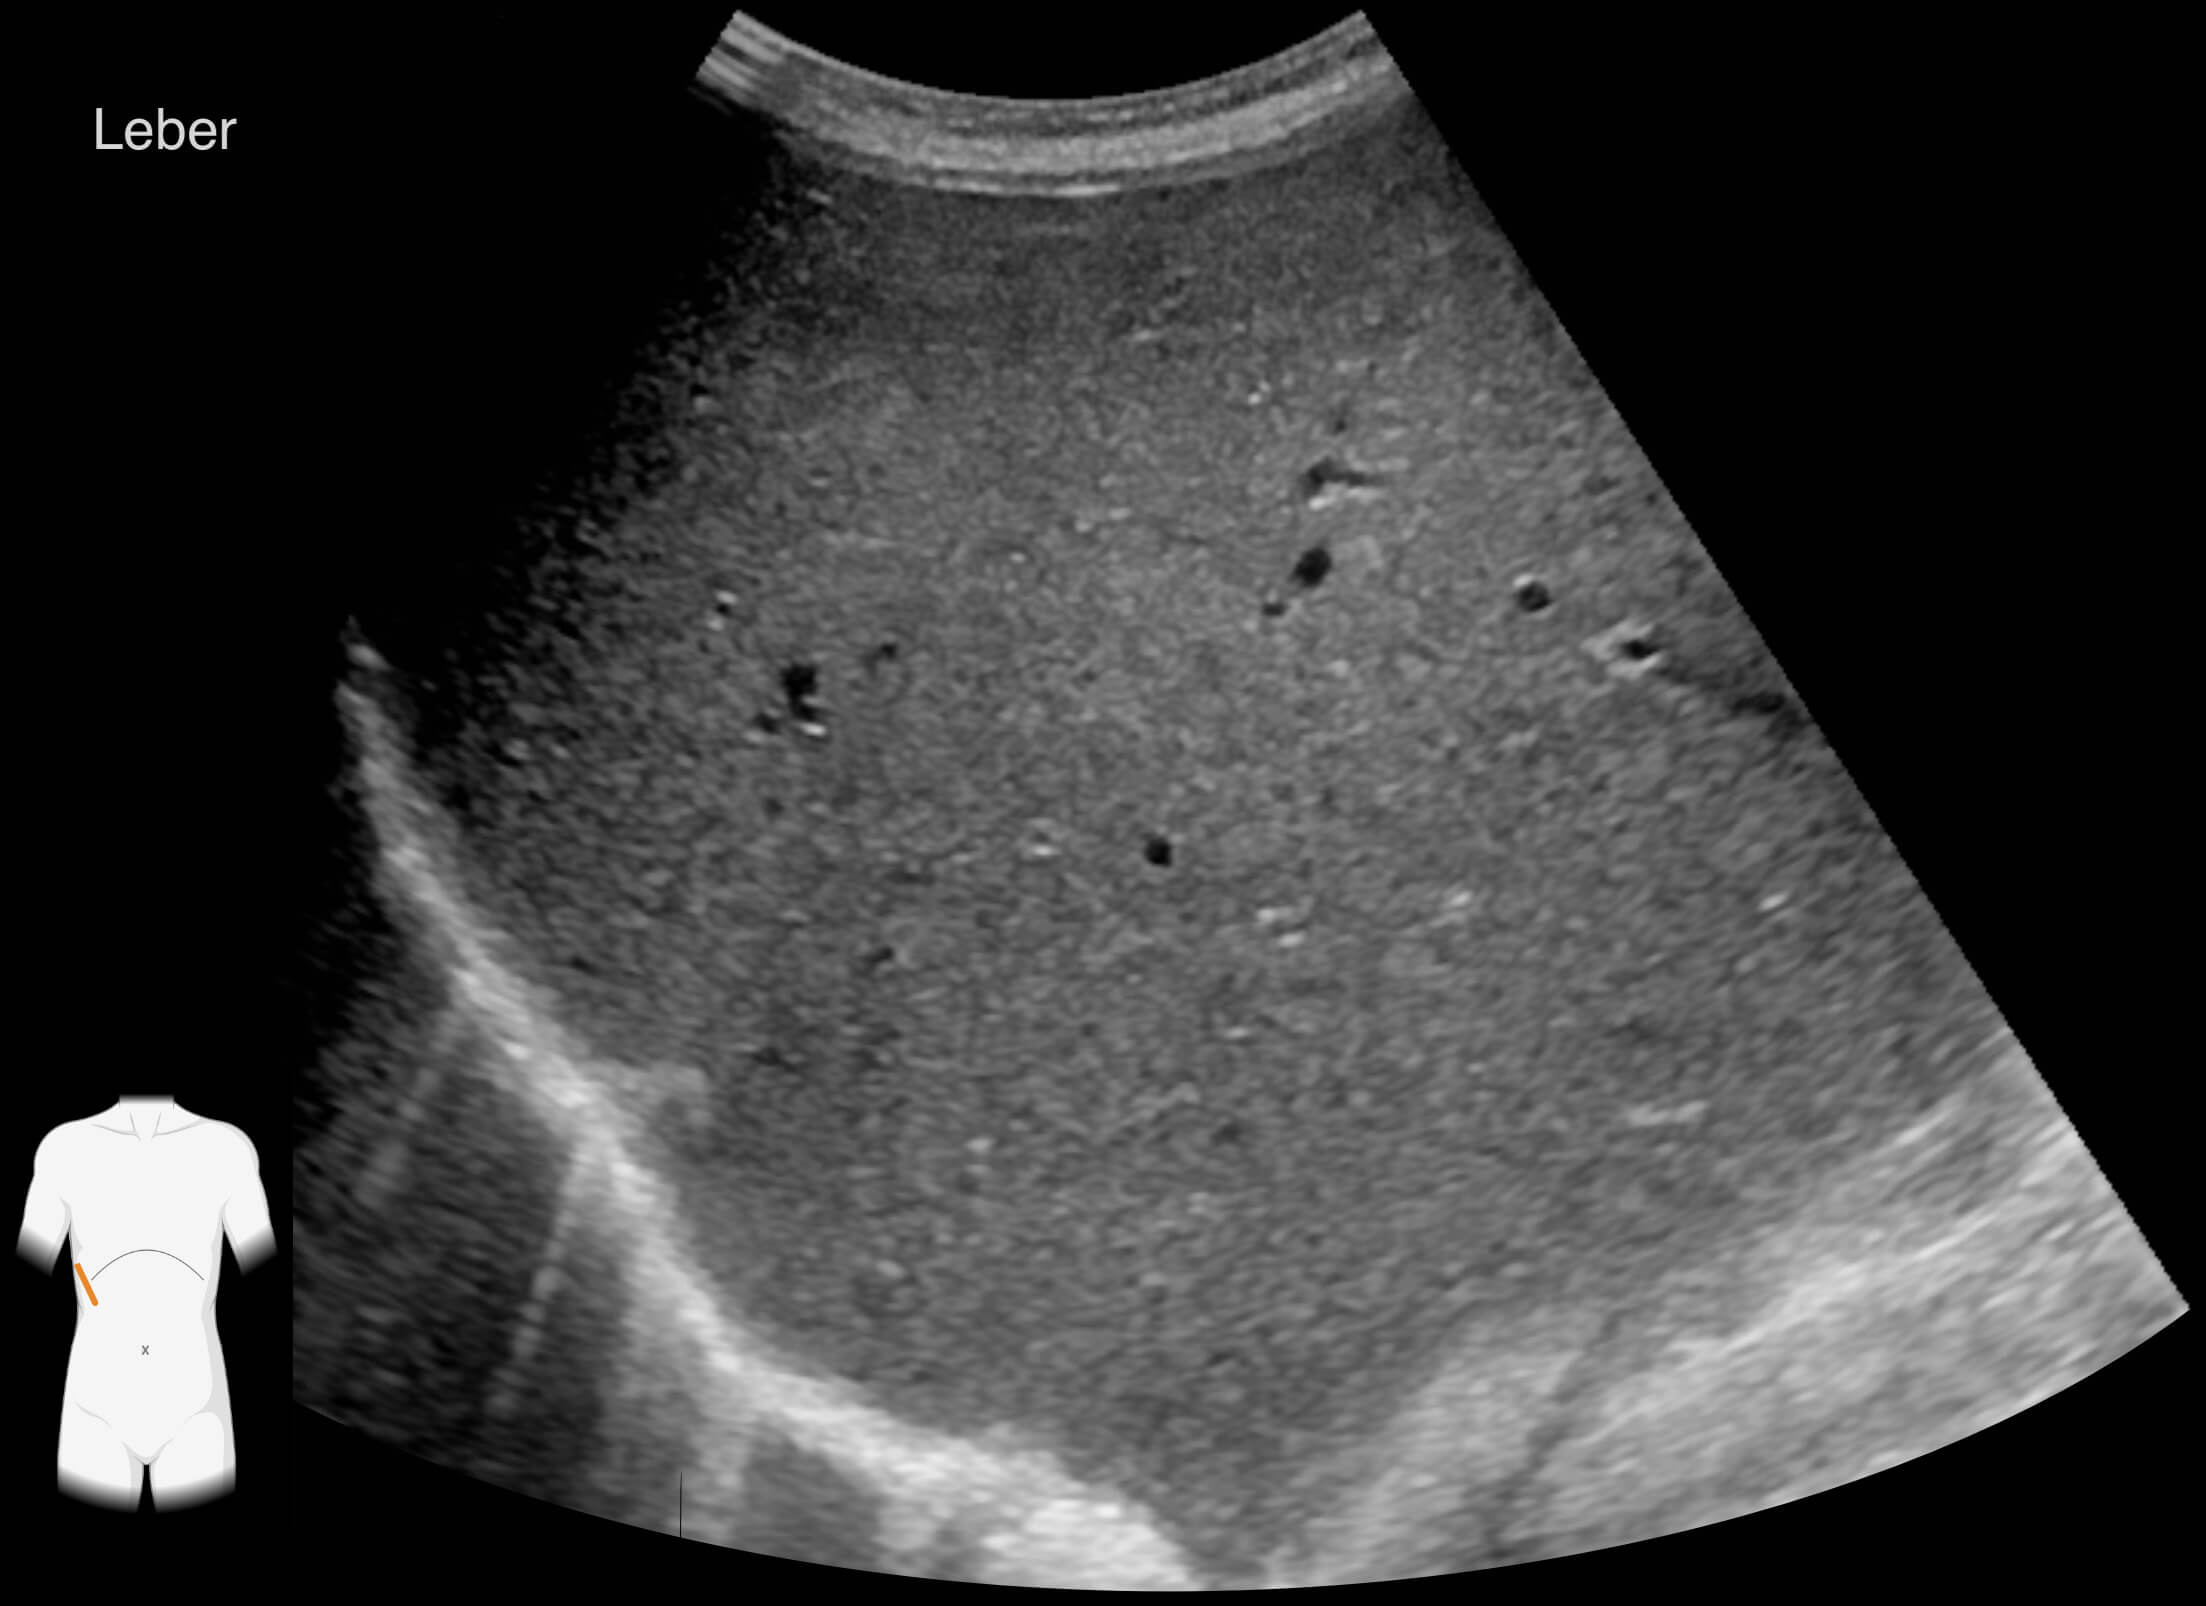

Die Ergebnisse der durchgeführten Untersuchungen kannst du dir hier anschauen:

Die Befunde geben eindeutige Hinweise auf die Erkrankung von Frau Lorenz. Wie bewertest du die Ergebnisse?